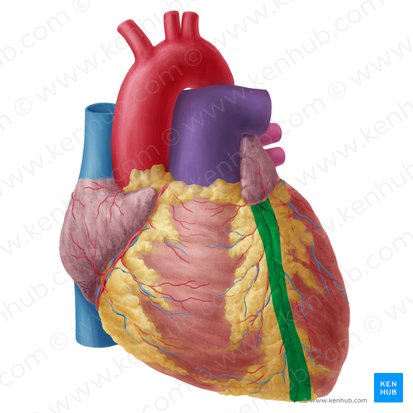

Anterior Interventricular Artery

Circumflex Branch

Coronary Artery

Anterior Interventricular Sulcus

Coronary Sulcus

Posterior Interventricular Sulcus/Artery

Marginal Branch

Circumflex Artery

Great Cardiac Vein